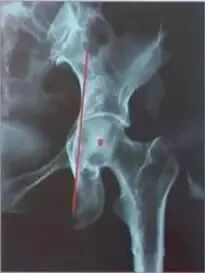

髋臼螺钉的放置区域:

安放位置大多选择在上图红色阴影部分(后上区)。